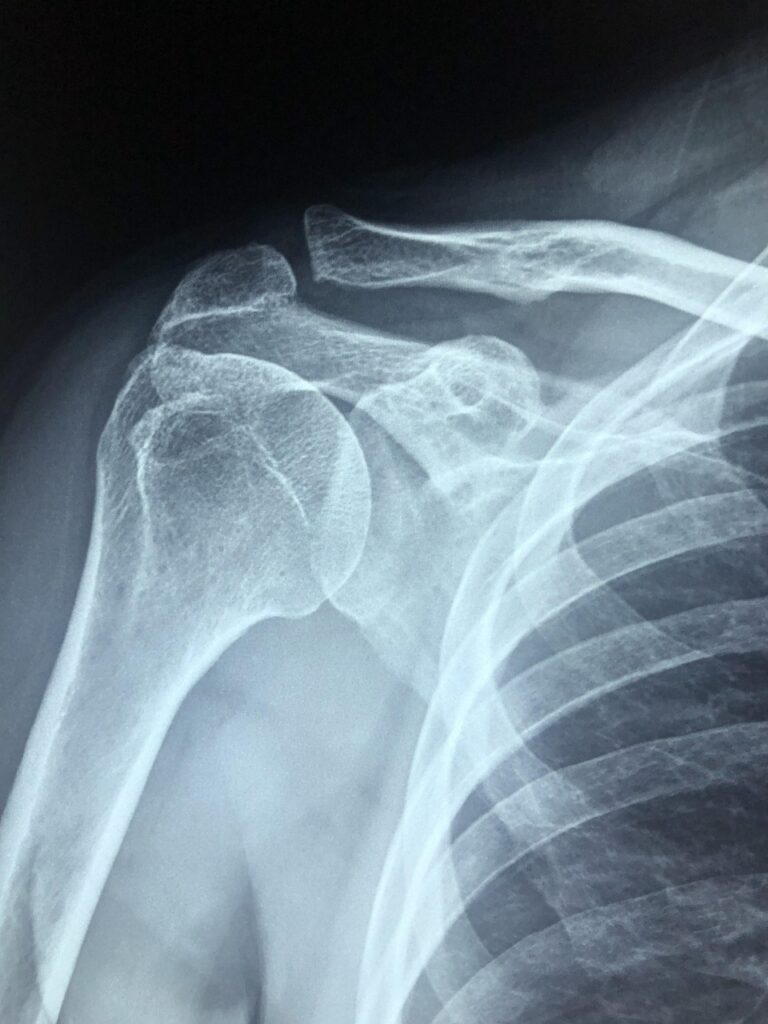

The Inverted Pear-Shaped Socket and the 25% Critical Size Defect

Background: Steve Burkhart popularized the concept of the inverted pear-shaped socket. He found that if more than 1/4 of the bone was missing from the socket after a dislocation and a strictly soft tissue arthroscopic repair was performed to fix it, then these patients would be at high risk for recurrence of instability. His work established the concept of the 25% critical size defect: if a patient has more than 25% of their socket missing the surgeon should consider augmenting it somehow with bone.